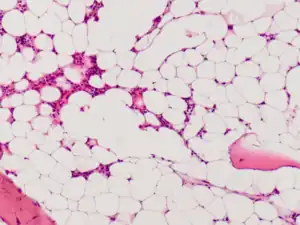

Micrograph of bone marrow taken from a person with aplastic anemia. The bone marrow is mostly fat cells with few blood forming cells.[2]

The cause is unclear in 65% of cases.[3] Other cases may occur following a viral infections, due to a genetic conditions such as Fanconi anemia, or exposure to chemicals, medications or radiation.[3][4] The diagnosis may be suspected based on low blood cells together with low reticulocytes and the absence of changes concerning for blood cancer.[3] The diagnosis is confirmed by a bone marrow biopsy finding mostly fat cells instead of blood forming cells.[5]